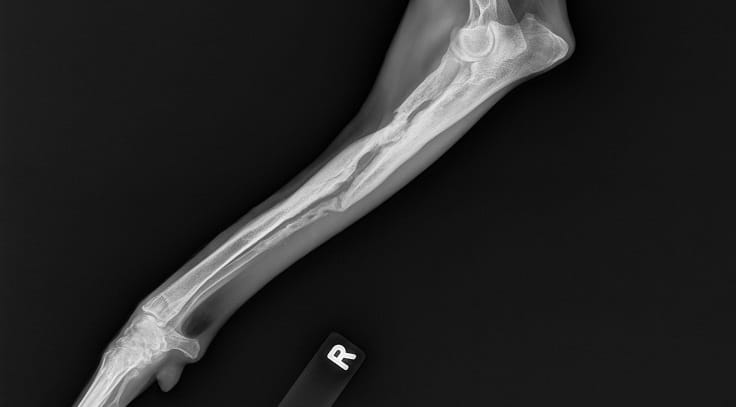

• Digital Radiology

Our hospital is proud to offer state-of-the-art digital radiology services. Digital x-rays are essentially film-less x-rays. Traditional x-rays use photographic film to capture images whereas digital x-rays use a digital image capture device (computer) to record the x-ray image.... Read more